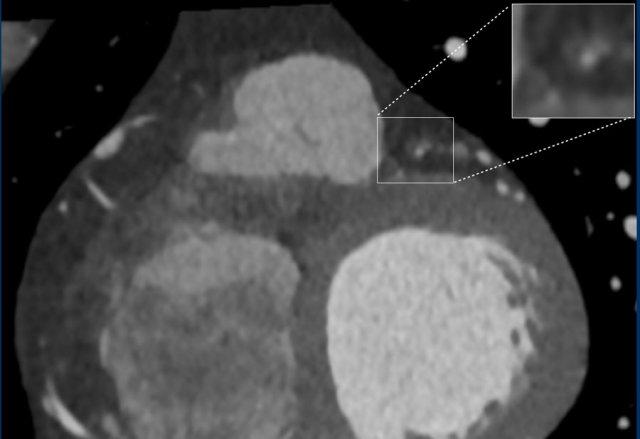

Same patient. First, study the CTA image.

How would you describe the findings?

The coronal image shows a central low-attenuation area around the lumen

of the LAD.

This low-attenuation area is surrounded by a higher attenuation

area.

This finding is the earlier discussed napkin-ring sign, which is a high-risk

plaque feature.

This patient classifies as CAD-RADS 4A/P1/HRP.

A: On the coronal image the so-called napkin-ring sign (dark area adjacent to the lumen, surrounded by a higher “ring-like” attenuation (white arrows). B: Tissue characterization on CT by HU number

Napkin-ring sign

The Napkin-ring sign is a qualitative high-risk plaque feature

on CTA (13).

It is defined as a central low-attenuation area adjacent to the coronary lumen

and a higher “ring-like” attenuation tissue surrounding this central area (14).

On histology, the area of low-attenuation corresponds to the necrotic core,

while the “ring-like” outer area correlates with fibrous plaque tissue.

The Napkin-ring sign is strongly associated with major adverse

cardiovascular events (15).